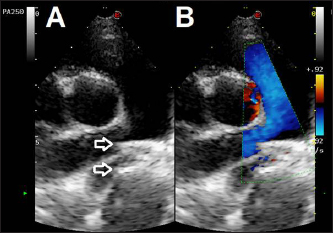

Fig. 4. Fluoroscopic sequence. (A) The first disc of the mVSD has been deployesd engaging the aortic side of the PDA and (B) then the waist and second disc fully extruded with the waist occluding the ostium and the second disc located into the pulmonary artery. (C) The stability of the device is tested with the push-pull “Minnesota wiggle” maneuver. (D) The device has been released

Fig. 5. Dual mode transthoracic echocardiography (right parasternal short axis view, optimized for duct visualization) 24 hours after surgery. The device discs (arrows) are correctly positioned and there is no evidence of residual shunt or pulmonary arterial obstruction given the laminar flow in the right pulmonary artery on CFM Doppler.

The device, previously screwed clockwise onto the delivery cable and introduced into its loader (SJM Amplaterz™ TorqVue™ Delivery 45° component 7 Fr. Loader and Delivery cable, AGA Medical Corporation, Plymouth, MN) was inserted into the delivery sheath and advanced carefully until the distal disc was expanded in the descending aorta near the PDA. The partially deployed mVSDO, attached delivery cable, and delivery sheath were then gently pulled back simultaneously until the distal disc engaged the ostium of the PDA and lodged in the ductal ampulla. The guiding sheath then was retracted further allowing expansion of the central component of the device within the PDA ampulla. The entire system was then retracted and subsequently, the proximal disk was expanded within the main pulmonary artery. The stability of the device was then tested with the push-pull “Minnesota wiggle” maneuver, the cessation of transductive flow and the correct positioning of the mVSD pulmonary disc were verified with transthoracic echocardiography, and the device was then deployed (Fig. 4). During the placement of the device all the parameters (saturation, invasive blood pressure, end-tidal CO2) remained within physiological ranges. Blood pressure increased (from 96/40/58 to 120/50/73 mmHg) while heart rate decreased (from 100 to 65 bpm) after occlusion of the PDA.

Echocardiographic checks at 3 and 24 hours showed complete PDA closure, correct positioning of the mVSDO (Fig. 5), and a clear reduction in left heart volume overload (LA: Ao decreased from 1.72 to 1.3, LVIDDN decreased from 2.49 to 2.43).